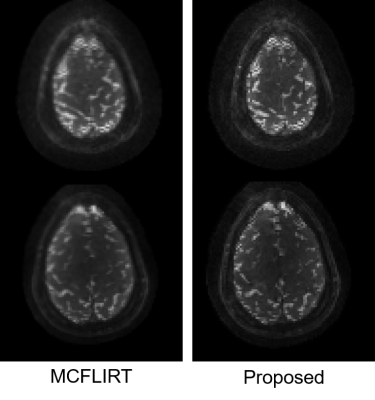

Fig. 2 shows the results of the phantom experiment. Compared with MCFLIRT, our method effectively reduced the blurring caused by the intra-frame motion. Fig. 3 displays the in-vivo reconstruction results, where the proposed method reduced blurring. Fig. 4 shows activation maps calculated from MCFLIRT and the proposed method. MCFLIRT falsely showed activation in the skull due to motion, whereas the proposed method accurately reflected voxels in the motor cortex.

Figure 3. Results of the in-vivo experiment. Two slices of the same time point are displayed, corrected by different methods. Similar to the phantom experiment, the proposed method effectively reduced the blurring.